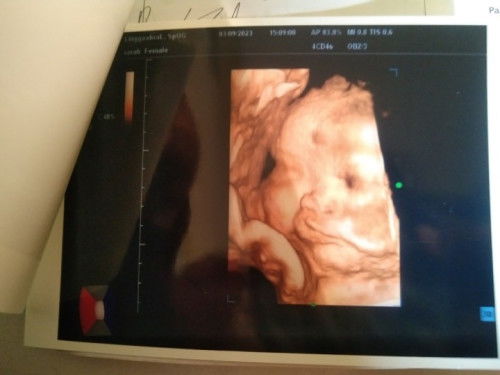

Apa terlihat seperti bibir sumbing .. bantu jawab ya mom

Bunda tadi siang aku usg , nah kata dokter nya sehat semua ga ada kekurangan apapun ketuban bagus aman ga ada lilitan tali pusar kepala udh dibawah juga tapi ada yang bikin aku sakit hati , ada temen aku komen foto hasil USG anak aku , dia bilang itu bibir nya SUMBING ya .. jleeeb langsung nyes dihati dibilanh gitu sama temen sendiri , apa iya bund anak saya begitu dokter ga bilang apa" dan sehat semua , jadi kepikiran terus ucapan manusia jahat kaya gitu 😭😭😭😭